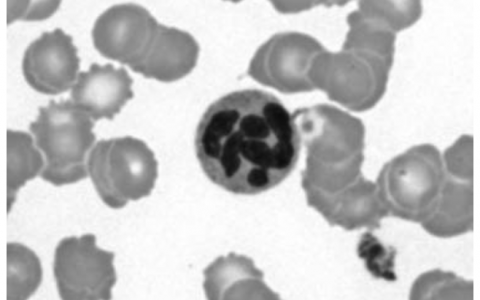

An infant with severe jaundice that is not corrected by phototherapy is in danger of developing kernicterus. This can occur in infants with Crigler-Najjar syndrome, a genetic disorder in which there is a near-complete deficiency of glucuronyl transferase. Which of the following laboratory findings would be expected in blood tests in an infant with Crigler-Najjar syndrome?

患有严重黄疸的婴儿如果不经光疗纠正,就有发展为核黄疸的危险。这可发生于患Crigler-Najjar综合征的婴儿,这是一种葡萄糖醛酸基转移酶几乎完全缺乏的遗传病。Crigler-Najjar综合征婴儿的血液检查应出现下列哪项实验室检查结果?

在Crigler-Najjar综合征中,缺乏葡萄糖醛酸基转移酶导致不能结合胆红素,从而导致非结合性高胆红素血症(高间接胆红素)。随着胆红素的累积,黄疸会变得更加严重,高水平胆红素会导致脑损伤。两种类型已被确定:1型(常染色体隐性)和2型(常染色体显性)。部分葡糖醛酸基转移酶缺乏症见于Gilbert综合征。

正确答案:D